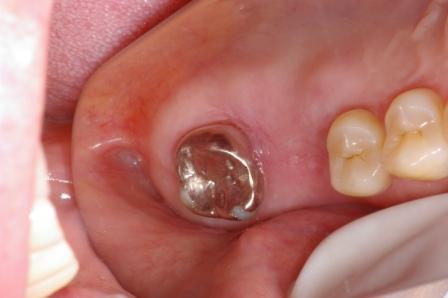

続いて奥歯のブリッジの症例です。

奥歯の2本を土台にしてブリッジを入れました。歯のないところにはブリッジを入れる治療が現在までの主流でした。

ただし、歯のないところにインプラント(人工の歯根)を植えると、土台の歯は削らないですみます。